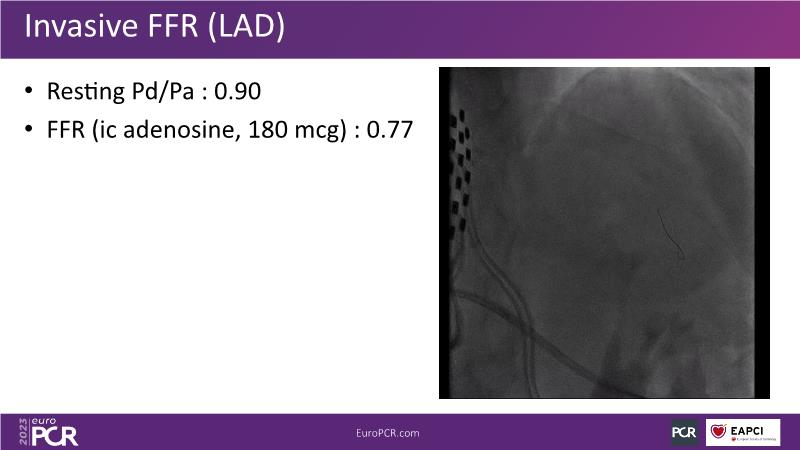

In this session, watch a case of intravascular imaging guided LM PCI from the ROLEX Registry, learn more about EBC MAIN 3-year results, see a case presentation with use of FFRangio, find out more about the KISS Trial, and follow the debates about all these learnings.

- To reflect on how FFRangio can support decision-making in complex PCI